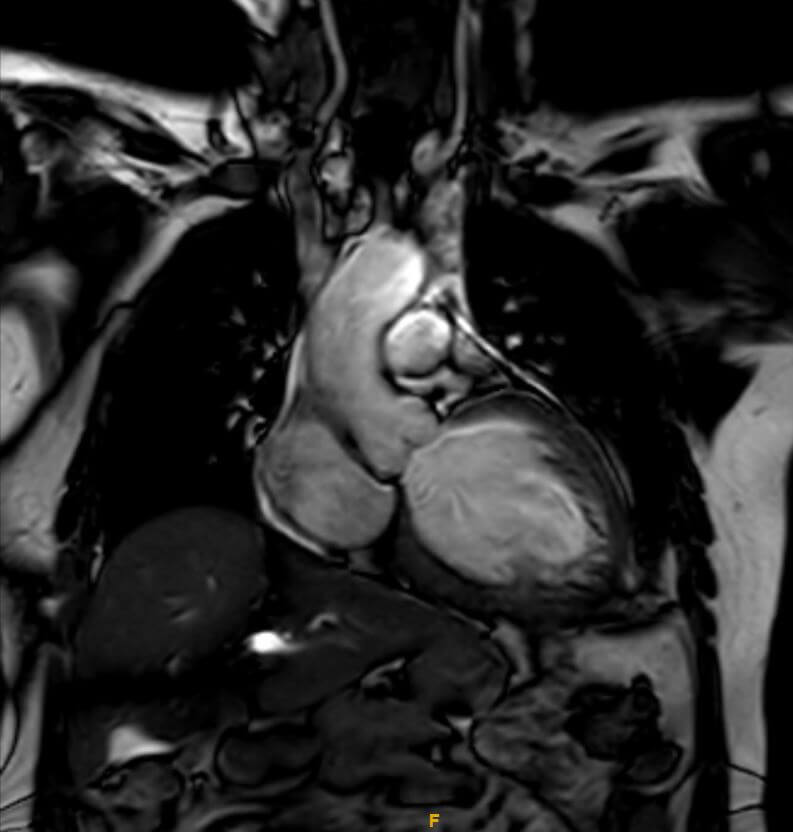

Cardiac Imaging

Cardiac imaging in radiology is a specialized field of medical imaging that uses various imaging techniques to visualize the heart and its surrounding structures.